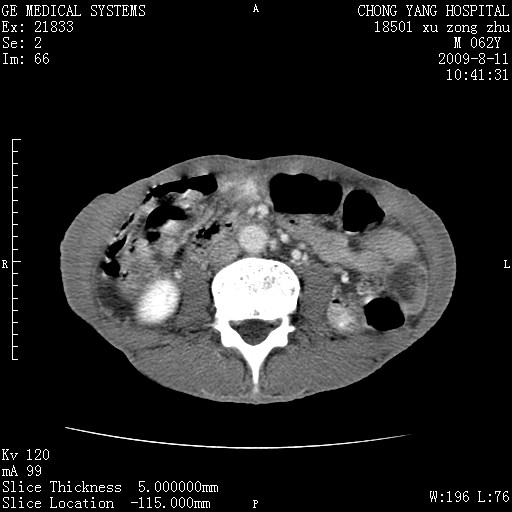

以下是引用杀毒软件在2009-8-11 16:35:00的发言:[br]肝内胆管扩张局限于左叶,胆管内有结石伴肝外胆管结石,胆管壁增厚呈弥漫性并发腹腔积液,胰腺边界模糊。[br][br]考虑---胆总管及肝内胆管结石继发胆管炎及胰腺炎,左肾下极囊肿,腹水。

以下是引用zjzjr在2009-8-11 17:35:00的发言:[br]肝内胆管扩张局限于左叶,胆管内有结石伴肝外胆管结石,胆管壁增厚呈弥漫性并发腹腔积液。[br][br]考虑---胆总管及肝内胆管结石继发胆管炎,左肾下极囊肿,腹水。